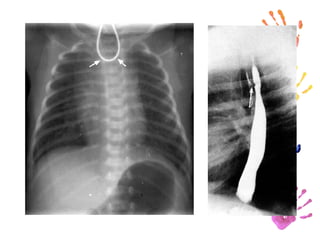

Diagnóstico. Introducir un catéter French blando 5 u 8 en el esófago hasta que encuentra una obstrucción, en ocasiones se puede enrollar en una bolsa ciega y crear falsa impresión. Una placa simple confirma la posición de la sonda y demuestra la bolsa esofágica superior ocupada por aire.

Diagnóstico.